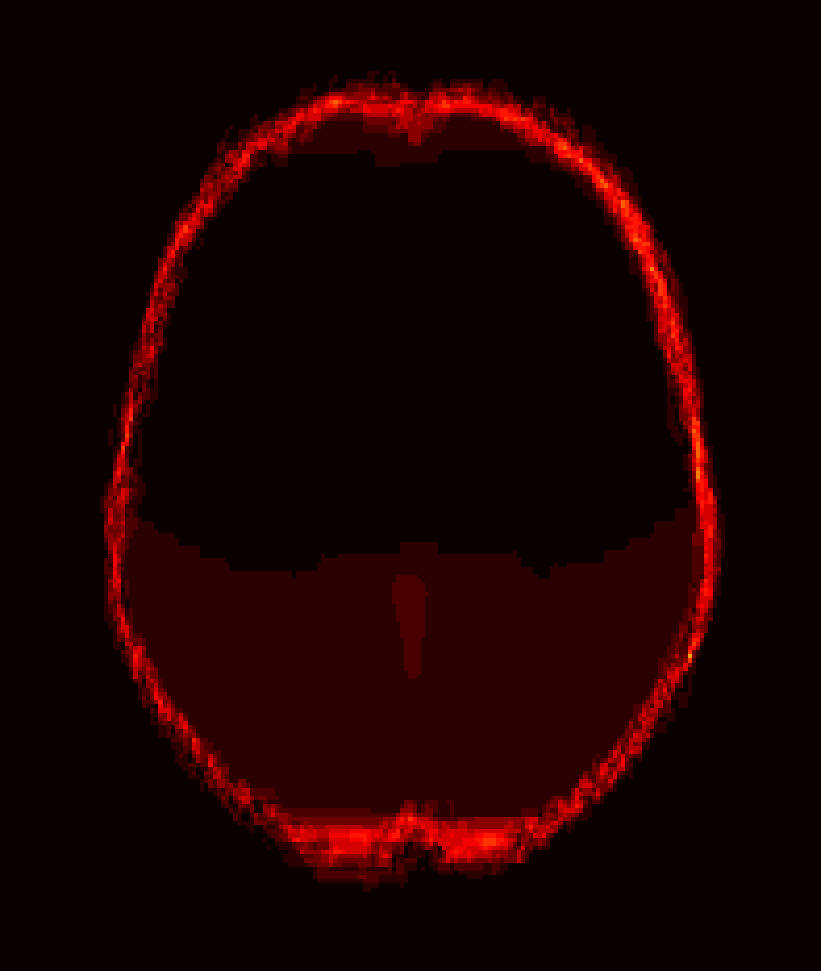

Fig. 1 shows example images from each dataset to illustrate image variability. IBSR and LPBA40 contain images from normal subjects and include large portions of the neck; BRATS has very low out-of-plane resolution; and the TBI dataset contains large pathologies and abnormal skulls.

Refer to caption

Figure 1: Illustration of image appearance variability on a selection of images from each (evaluation) database. From top to bottom: IBSR, LPBA40, BRATS and TBI.